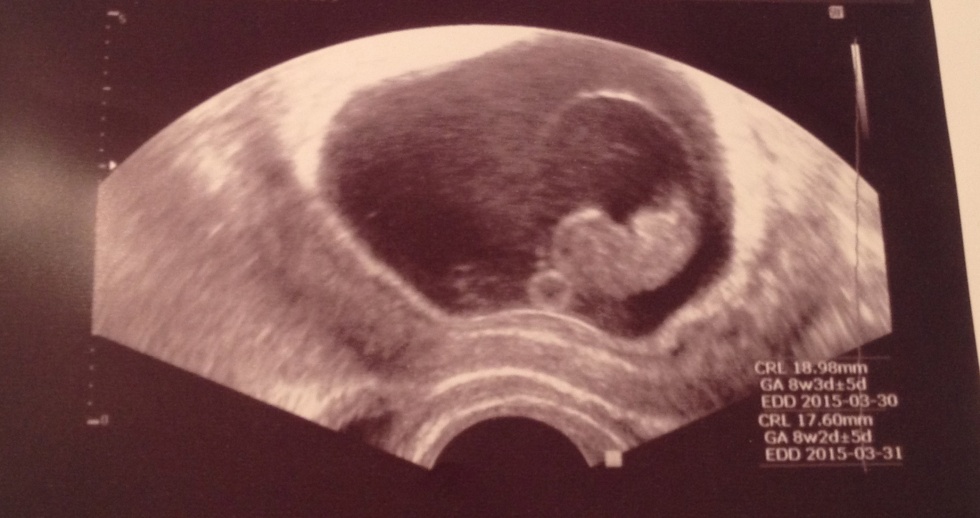

v. 9